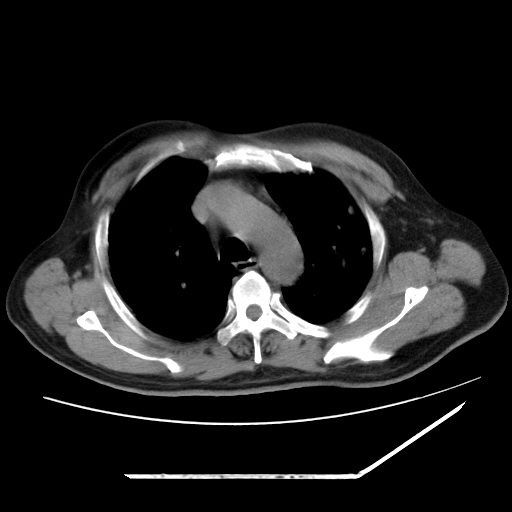

男,57,畏寒,发热

两肺野多发大小不一高密度灶,纵膈内见肿大淋巴结,要考虑转移瘤可能。双侧胸腔少量积液。

1)考虑两肺感染性病变(金黄色葡萄球菌肺炎?);建议抗炎治疗后复查排除其他。2)双侧少量胸腔积液。

血源性肺脓肿,除外转移瘤